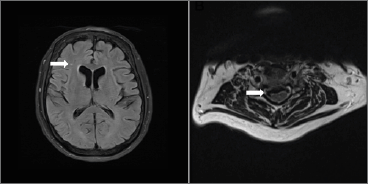

Creatine kinase levels were within normal limits (Tab. II). Autoimmune and paraneoplastic testing performed at Mayo Clinic Laboratories (MCL) was negative (Tab. III). Pyruvate concentration in the blood was elevated at 1.8 mg/dL [reference range, 0.7-1.4 mg/dL (Tab. II)]. Pulmonary function testing showed a restrictive pattern with a forced vital capacity of 76%. MRI of the brain suggested chronic cerebral vasculopathy (Fig. 1A), consistent with previous observations in patients with SPG7-related disorders 13,14. MRI of the cervical and thoracic spine demonstrated multilevel degenerative changes that were associated with moderate to severe cervical canal stenosis (at the level of C5-C6) with no intrinsic spinal cord deformity (Fig. 1B). Electrodiagnostic studies [including electromyogram (EMG)] revealed diffuse neurogenic changes and myopathic appearing motor unit potentials (Tab. II).

Figure 1. Axial T2-FLAIR sequence of brain MRI showing hyperintense lesion in the right corona radiata (white arrow) consistent with chronic cerebral vasculopathy (A) as previously described in patients with SPG7-related disorders 13,14. Axial T2 sequence of cervical spine MRI showing evidence of broad posterior disc osteophyte complex (white arrow) leading to moderate to severe cervical canal stenosis with no intrinsic spinal cord deformity at the level of C5-C6 (B). Abbreviations: FLAIR: fluid attenuated inversion recovery; MRI: magnetic resonance imaging.